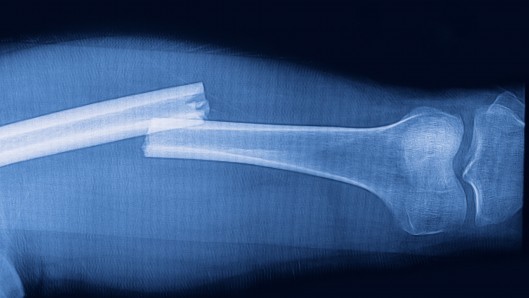

В последние годы ученые уделяли много внимания изучению использования различных систем имплантатов для сращивания раздробленных костей. Британские ученые из Саутгемптонского университета разработали новый вид пластиковой субстанции, которая способствует росту костной ткани.

Ячеистая структура материала, вживляемого в сломанные кости, пропускает через себя кровь, позволяя стволовым клеткам костного мозга приклеиваться к материалу. «Чужие» клетки принимаются за «свои», их количество постепенно увеличивается, заменяя собой биоразлагаемый пластик.

По мнению профессора Ричарда Ореффо, исследовательская группа использовала новую методику. Для получения легкого и прочного имплантата ученым понадобилось смешать и проанализировать сотни комбинаций пластических масс. Конечный вариант образуют три нетоксичных пластика, способствующих росту костной ткани. Инновационный материал был успешно протестирован на животных, в ближайшее время планируется провести испытания на человеке.